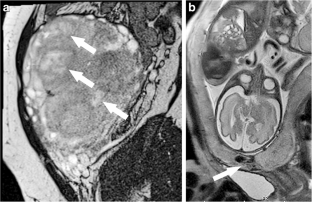

Fig. 1

Fig. 2

Fig. 3

Fig. 4

Fig. 5

Fig. 6

Fig. 7

Fig. 8

Fig. 9

Fig. 10

Fig. 11

Fig. 12